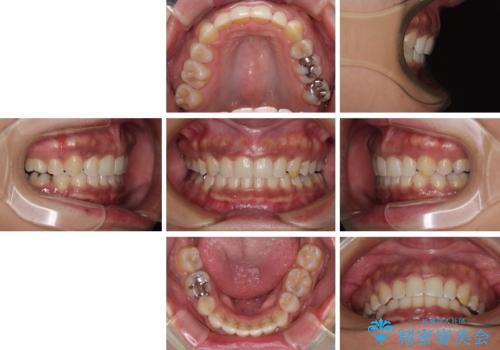

抜歯矯正で口が閉じやすく|ディープバイトと叢生を改善した症例

- 下顎前歯部には叢生が認められ、口を自然に閉じにくい状態でした。また、噛み合わせが深い「ディープバイト」の状態で、見た目だけでなく将来的な奥歯への負担も懸念されました。

口元の突出感を改善するため、上下左右の小臼歯4本を抜歯する矯正治療を計画しました。

抜歯矯正は「歯を抜くのが不安」と感じられる方も多いですが、

適切な診断と治療計画により、口元・噛み合わせ・将来的な安定性を同時に改善することが可能です。